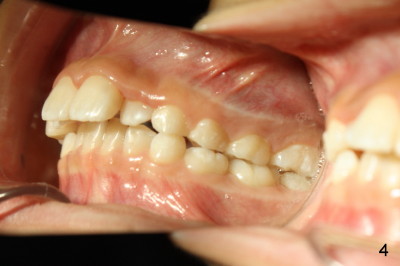

Eight-year-four-month-old boy shows early signs of Class II Division I malocclusion (Fig.2-5).  Panoramic X-ray was taken when he was 5 years 10 months old (Fig.1).

Is there any indication for phase I ortho (interceptive treatment)?  In my opinion, early orthodontics will improve appearance.  Additional Class II retraction may change canine and molar Class II occlusion into Class I so that the mandible may develop normally before permanent dentition.  If the early treatment is not done until permanent dentition as parents hope, it is most likely that orthodontics will be conducted with extraction at least two upper bicuspids.  The father has typical Class II Division I malocclusion.  What do you think?  Thanks.

-Boys grow later and longer than girls and my ability to modify growth lasts longer as a result.  It can often be done at an age where the permanent teeth are in.  Two upper bi's defendable for xs. overjet/dental protrusion, whereas I like the Herbst for Class II growth modification of skeletal nature/mandibular deficiency.

2nd reply Also Xin in your case of the 8 y.o. boy, I could make the argument that the lingually positioned #7 and #10 may ultimately restrict the lower jaw from growing normally anteriorly.  Their position may very well indeed be in the way.  Check out occlusion from your pictures.  I can explain better in person perhaps.